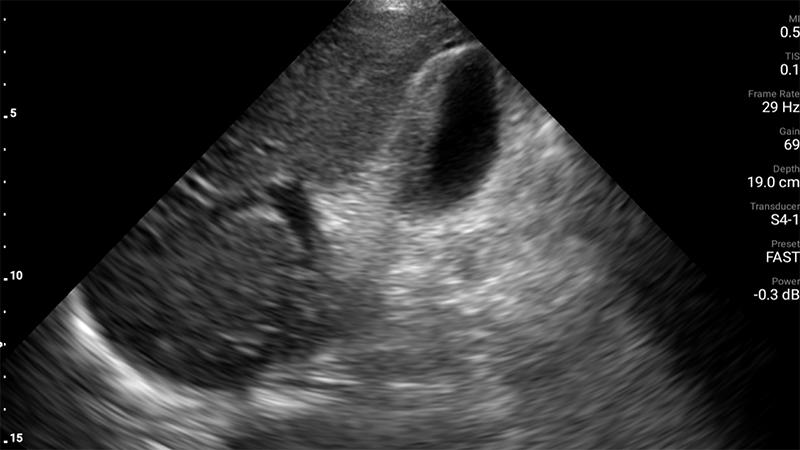

Figure 49. Mild hydronephrosis seen on long axis view of the kidney. Note the mild dilation of the renal pelvis and calyces and the lack of color Doppler flow over the anechoic (black) dilation of the renal pelvis.

Figure 50. Moderate hydronephrosis seen on long axis view of kidney without a change in the thickness of the renal cortex.

Figure 51. Severe hydronephrosis seen on long axis view of the kidney. Note the severe dilation of the renal pelvis and thinning of the renal cortex, as well as the dilated ureter extending to the right of the image.